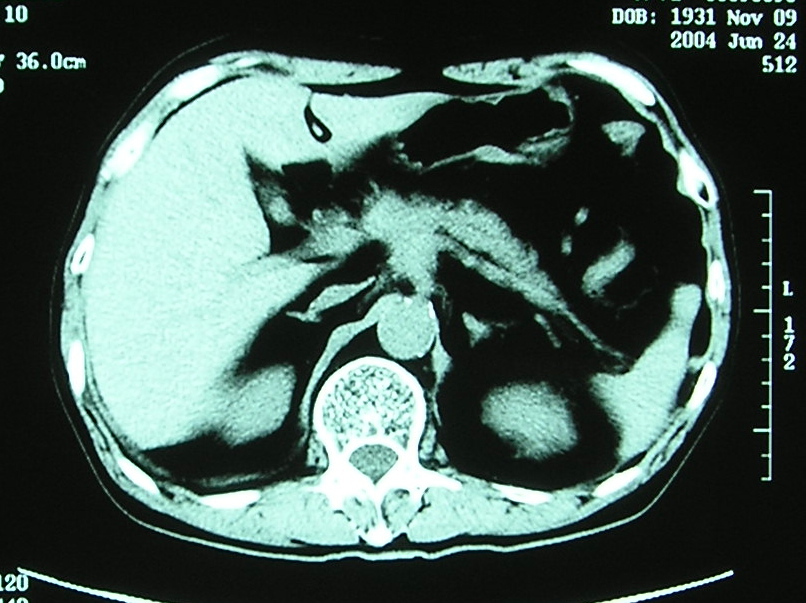

膵癌

背部痛にて偶然発見。

膵頭部に腫瘍をみとめる。